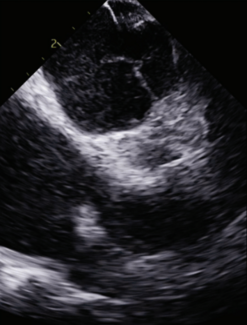

This report describes a successful single-procedure use of pulsed field ablation and left atrial appendage occlusion, guided entirely by intracardiac echocardiography, as a potential one-stop approach to complex AF management.

Dr Weisman discusses his approach for a 4-dimensional intracardiac echocardiography-guided approach to left atrial appendage occlusion procedures.